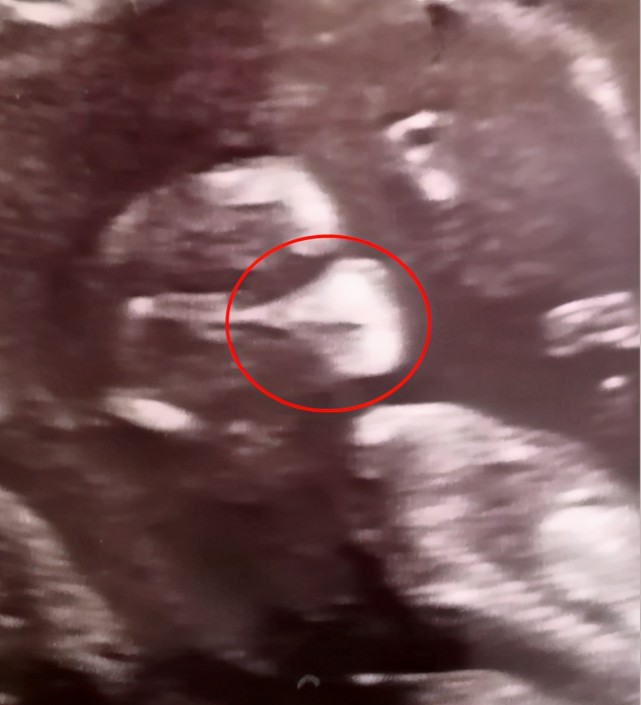

每日一图:分享无脑儿一例,论产检的重要性 关注 如图,感谢站友

筛查的意义:可初步筛查无脑儿,露脑畸形,严重脑膨出,严重胸腹壁缺损